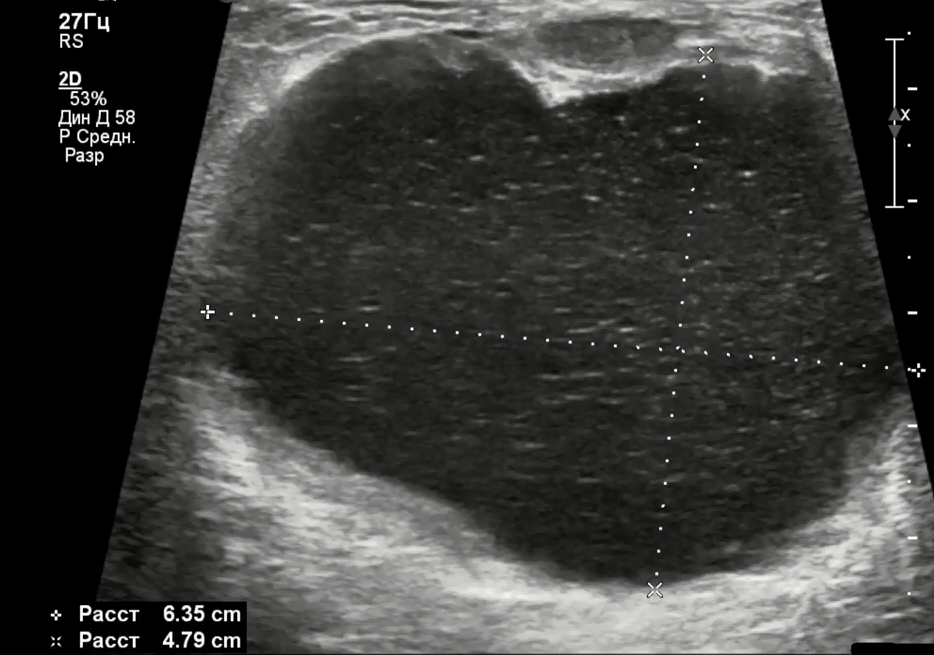

На ультразвуковом исследовании рак молочной железы может проявляться в виде образования, имеющего четкие или нечеткие контуры, а также зону с высоким или низким уровнем эхогенности. Часто можно наблюдать включения, которые свидетельствуют о наличии жидкостных, некротических или кальцинированных образований.

Важно отметить, что рак может выглядеть как солидное образование, так и в виде множественных мелких уплотнений, поэтому интерпретация УЗИ требований высокой квалификации специалиста, который должен учитывать все возможные характеристики обнаруженных изменений.

На ультразвуковом исследовании молочной железы опухоли зачастую имеют округлую или овальную форму, а границы варьируются от четких до размытых. В некоторых случаях могут обнаруживаться кальцификаты, но вторичных изменений, как правило, не наблюдается. Геморрагические проявления внутри опухоли также не являются типичными.

На ультразвуковом исследовании аденоидно-кистозный рак молочной железы обычно представляет собой нерегулярные, гетерогенные или гипоэхогенные образования с незначительной васкуляризацией, анализируемой с помощью цветного доплеровского изображения.